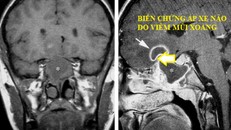

(Ngày Nay) - Viêm xoang không chỉ xảy khi thời tiết khô, lạnh, thay đổi thường xuyên, tỷ lệ người mắc bệnh còn gia tăng trong mùa hè. Một trong những nguyên nhân chính là sự suy giảm sức đề kháng của niêm mạc hệ thống mũi xoang mà thủ phạm là việc sử dụng điều hòa không đúng, đi bơi lội.

Viêm xoang là 1 căn bệnh phổ biến ở Việt Nam, bệnh thường mãn tính, gây khó chịu cho người bệnh. Để khắc phục, bạn hãy tìm hiểu về những bài thuốc nam trị xoang hiệu quả dưới đây!